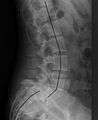

| X-ray of the lateral lumbar spine with a grade III spondylolisthesis at the L5-S1 level. | |